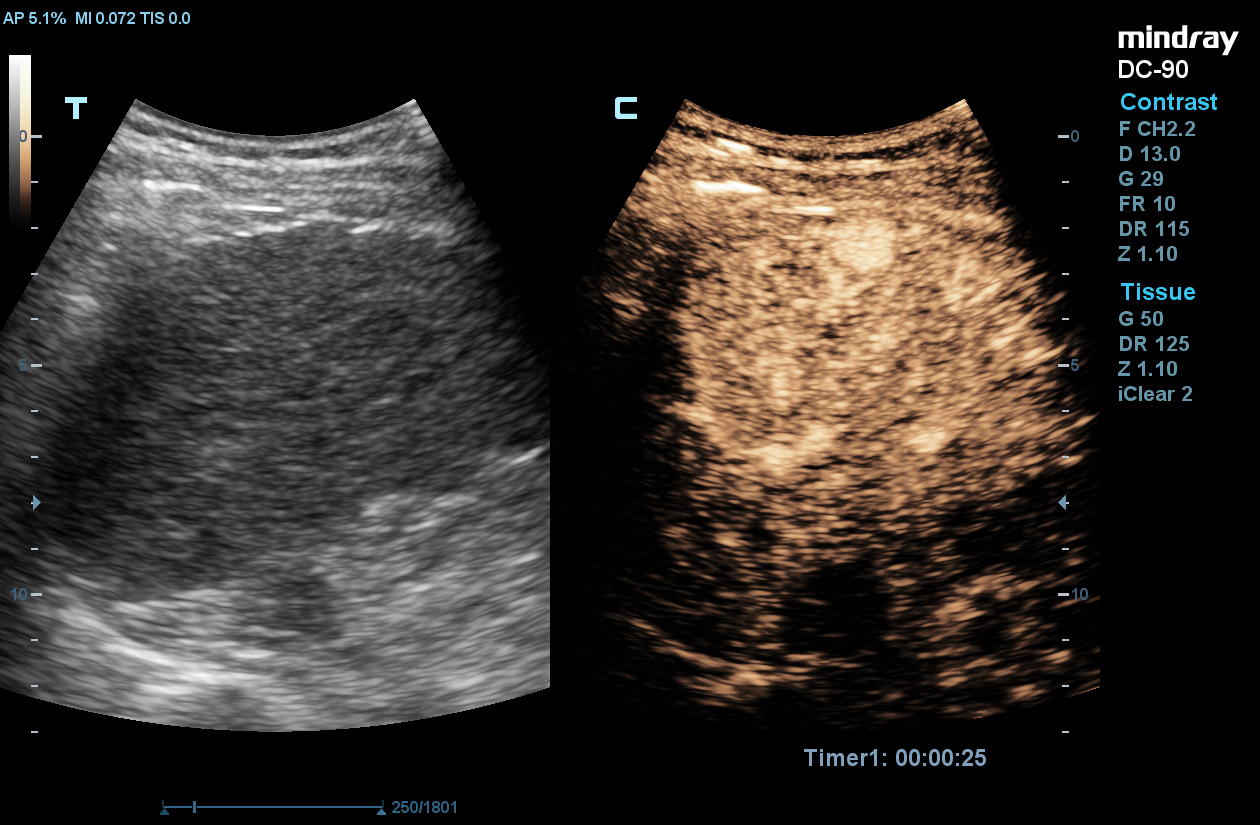

UWN+ CEUS

Mindray’s second generation Ultra-Wideband Non-Linear (UWN+) contrast enhanced ultrasound (CEUS) imaging uses both harmonic and fundamental signals to improve contrast and temporal resolution during CEUS studies. X-insight, the technology that powers the DC-90, allows for a longer duration of perfusion in the tissues.